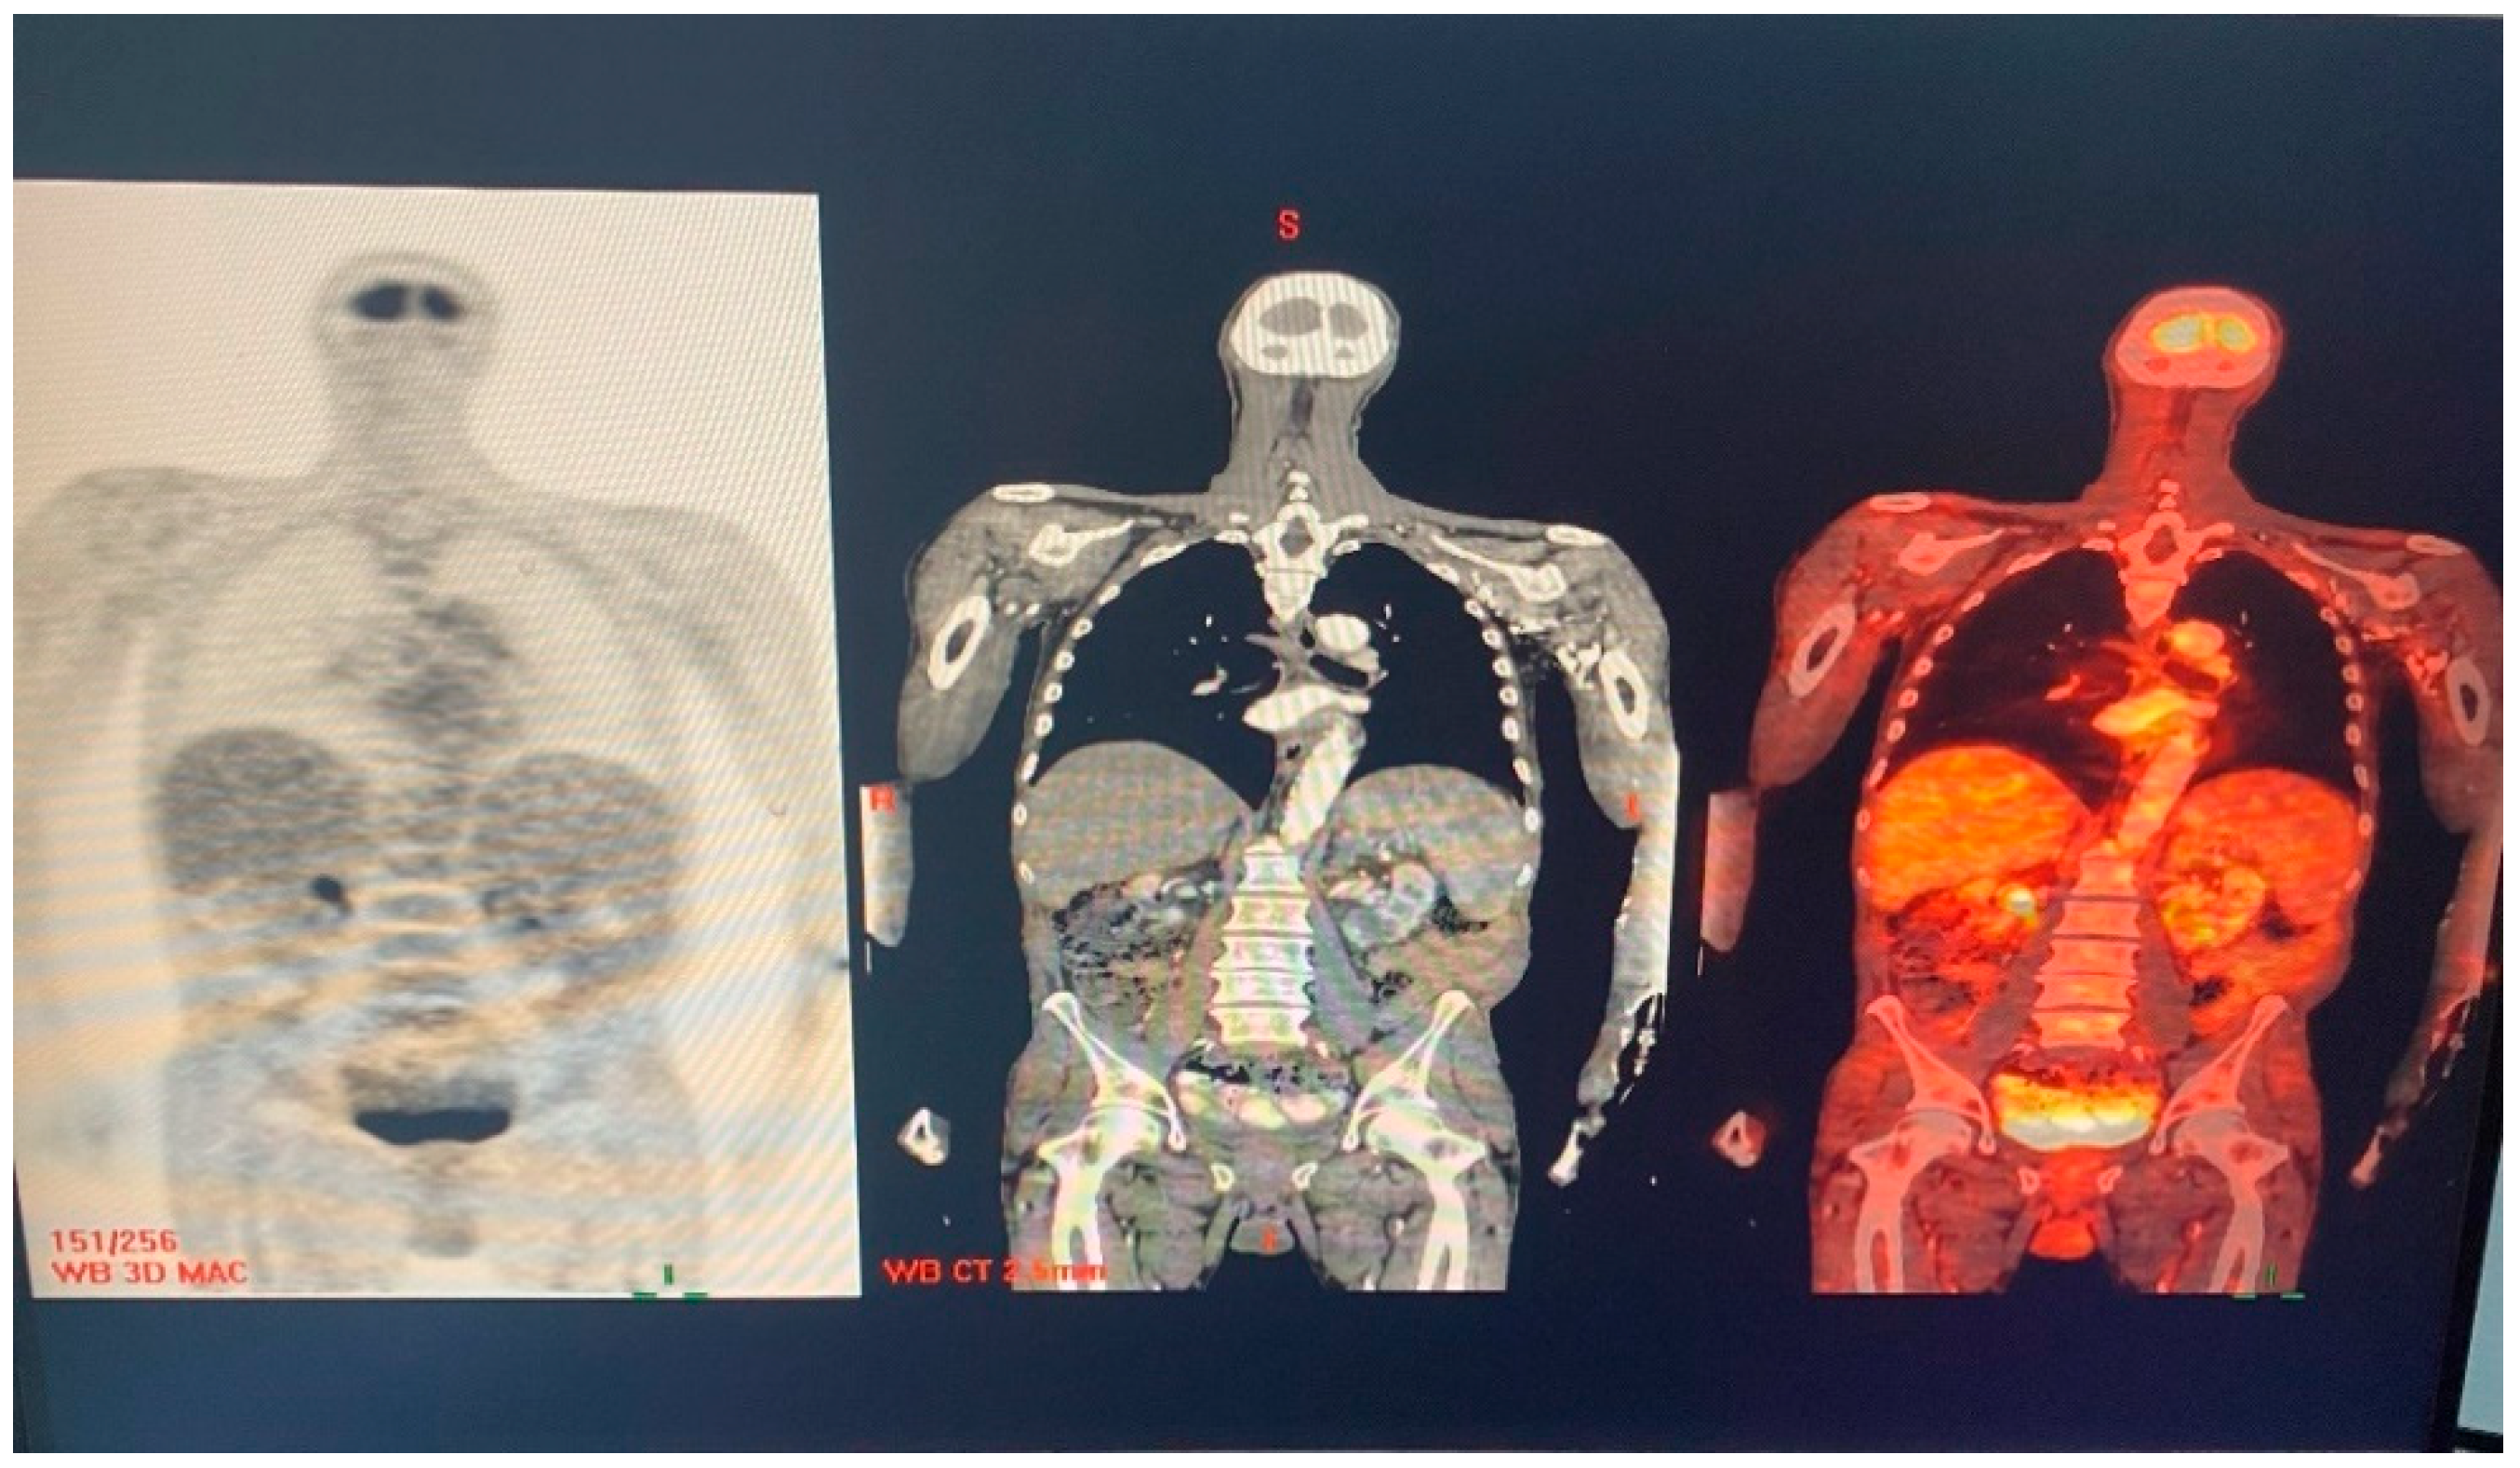

Repeated Q fever serology showed no further elevation in phase I titers (Table 1). The patient underwent a positron emission tomography CT (PET-CT) scan, which was interpreted as normal without any enhancement (Figure 4). Repeated third TEE 2 months after the termination of 18 months of antibiotic treatment of Coxiella burnetii demonstrated mild mitral regurgitation and no vegetation on the mitral and the aortic valves.

Figure 4.

PET-CT scan showing no pathologic enhancement.